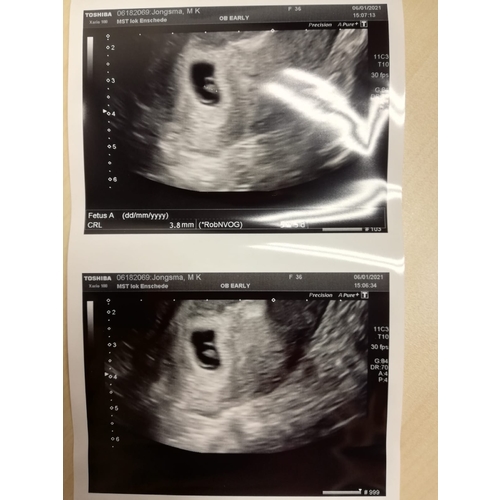

Dit was bij 6-7w

6 weken met kloppend hartje